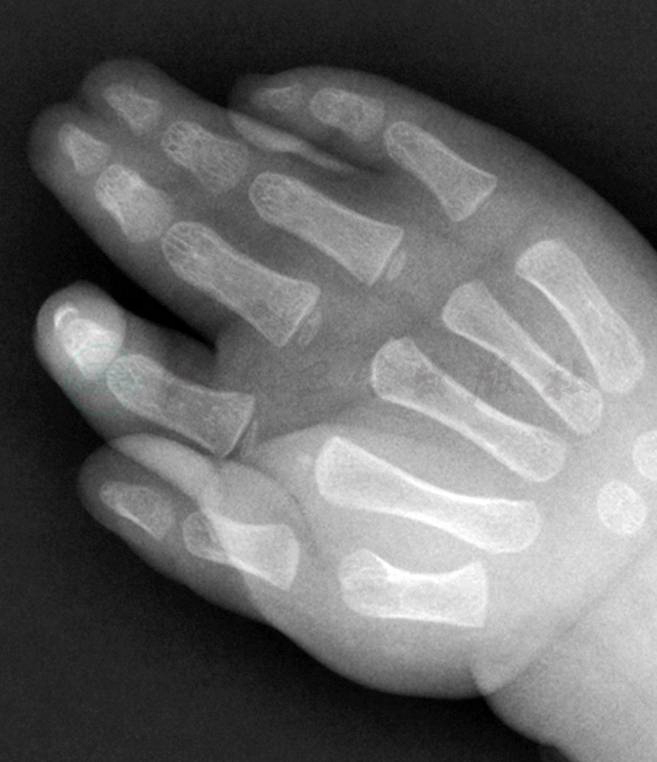

并指畸形表现为两个或两个以上手指的组织结构完全性或不完全性相连,可单纯的皮肤并连(图1),也可伴有指骨或掌骨融合,并合并各种形态的指甲畸形(图2),因而不能用一种简单的表现形式来描述。临床上常常根据并指畸形的形态、部位、组织结构以及伴随畸形,采用不同的分型方法来描述。

图1单纯皮肤相连的第3、4指并指畸形